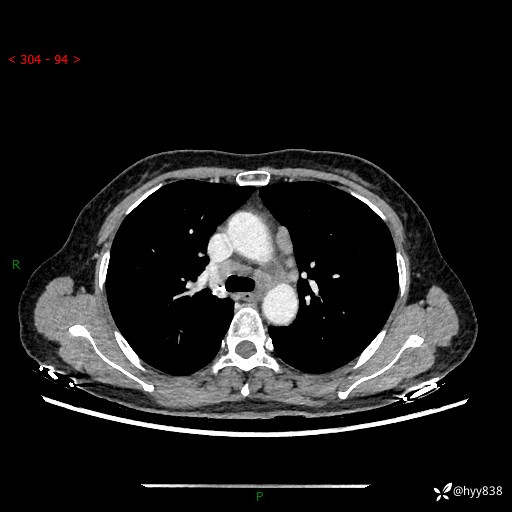

【患者信息】:58岁/女

【主诉】:体检发现肺结节

【检查】:胸部CT平扫+增强

结节病 (44)

小细胞癌 (19)